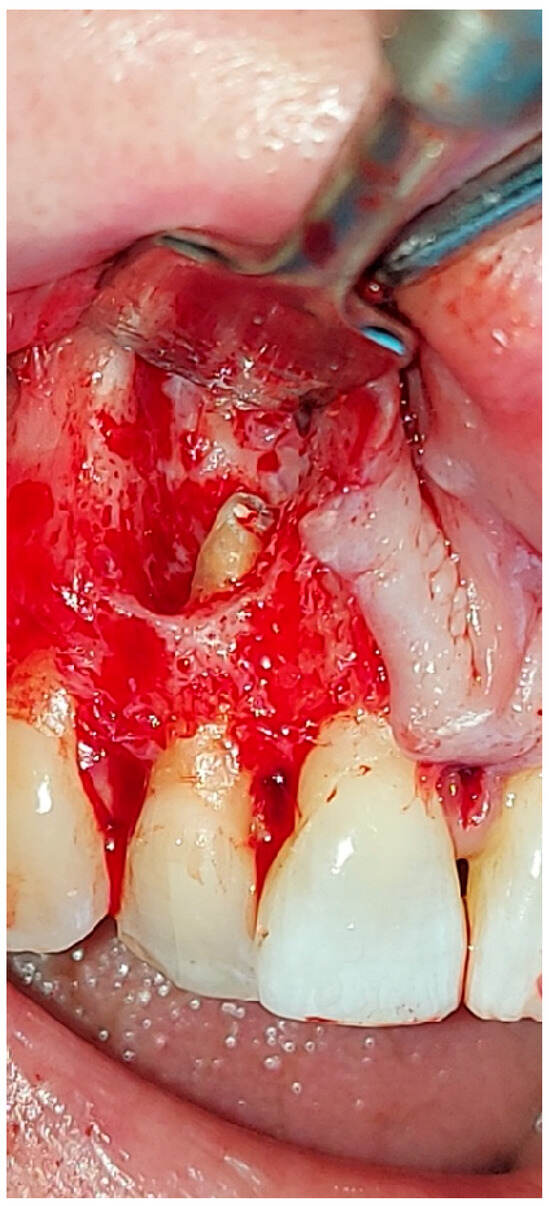

2. The Case